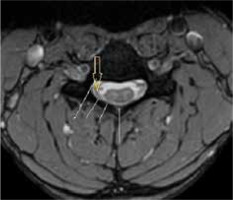

Figure 9

T2* axial section of the same patient in the neutral position showing loss of attachment from subjacent lamina, which is more than one-third and is better visualized than on T2W axial sections (arrow)

LOA of posterior dura with anterior displacement was seen in all the patients (100%) on flexion MRI (Figure 7). LOA involved the whole of the posterior dura (bilateral) in 13 patients (76.4%) and only one side in 4 patients (23.5%). Maximum LOA was seen at the C6 level in 10 patients (58.8%), followed by C5-6 intervertebral disc level in 5 patients (29.4%), and C5 and C6-7 level in one patient each (5.8%). This LOA of the posterior dura was seen in 11 patients (64.7%) on neutral position MRI, as well (Figures 8 and 9). On evaluating axial T2W and T2 FFE images for LOA of posterior dura, mutual consensus was reached by 2 radiologists that it was better visualised on T2 FFE images (Figure 9). The mean thickness of this LOA on flexion was 3.7 ± 0.66 mm (mean ± 2SD).

Asymmetrical lower cervical cord atrophy is the most important imaging feature on neutral MRI that can suggest the diagnosis of HD. LOA can also be seen on neutral MRI. On evaluating neutral T2W axial images in our study, LOA was seen to be present in 64.7% of the patients. As per Chen et al. [13], LOA was the most effective finding in the diagnosis of HD in neutral position MRI, with sensitivity and specificity greater than 93.5%; however, Lehman et al. reported lower sensitivity (70%) of this finding [18].